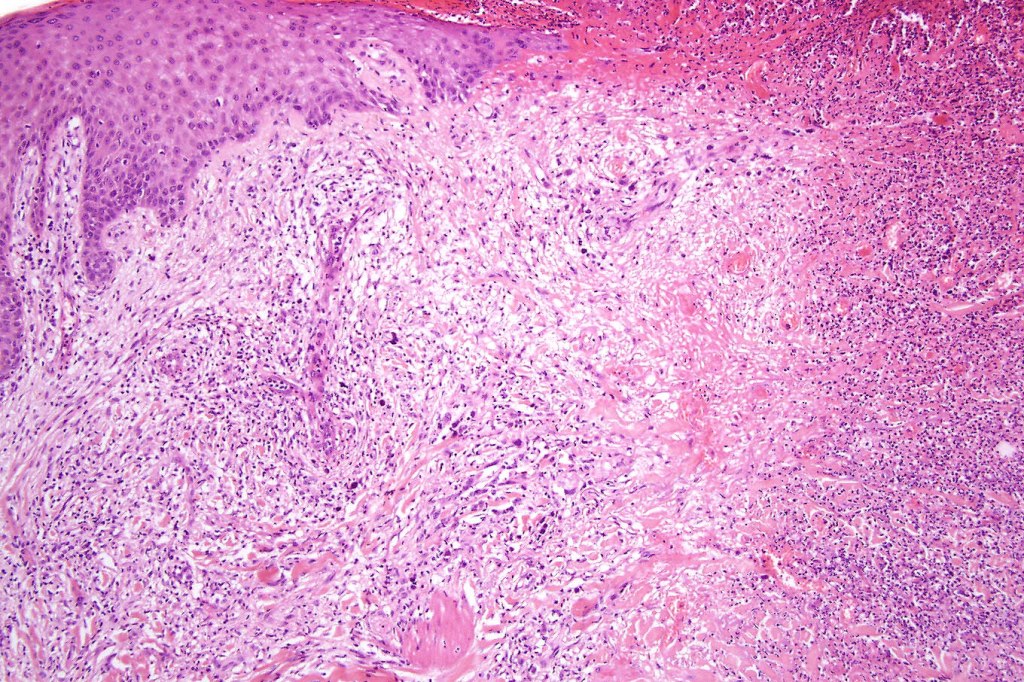

Histological features

•Subdivided into 5 major & several rarer variants

•Type A: 75-80%, wedge shaped infiltrate with base uppermost, large, anaplastic cells with abundant cytoplasm and vesicular nuclei containing prominent nucleoli, can resemble Reed-Sternberg cells, conspicuous mitoses & background infiltrate of lymphocytes, plasma cells, histiocytes, neutrophils & eosinophils

•Variable epidermal necrosis, epidermotropism, edema, hemorrhage & vasculitis/thrombosis